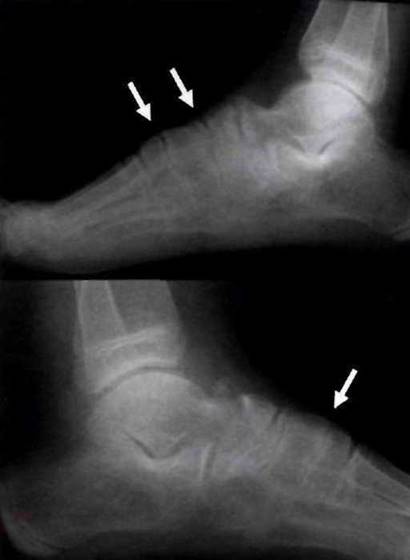

Рис. 23-11, Остеофиты в месте фиксации плантарной фасции к нижним краям пяточных бугров (указано стрелками) у больного ЮАС.

Рис. 23-12. Эрозии пяточной кости у больного ЮАС: А - рентгенограмма; Б - сцинтиграфическое исследование (значительное накопление радиофармпрепарата справа); В - компьютерная томография; Г - прогрессирование рентгенологических изменений с формированием остеофитов верхнего и нижнего краёв пяточной кости при исследовании в динамике через 4 года.